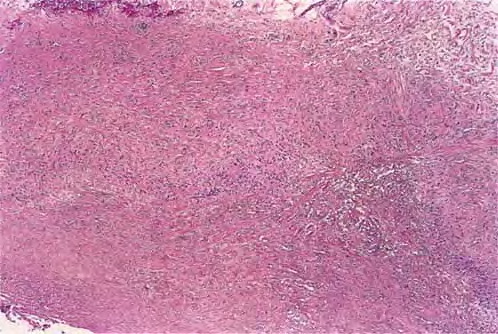

The diagnosis is best made at low magnification. Changes are usually observed in the upper and middle dermis, although any part of the dermis or subcutis can be involved. The characteristic histopathologic finding is a lymphohistiocytic granuloma associated with varying degrees of connective tissue degeneration and mucin deposition. The inflammatory infiltrate may have a palisaded or interstitial pattern, or a mixture of both patterns.Occasionally, a sarcoid-like pattern with large epithelioid histiocytes is seen.

The typical appearance is of single or multiple foci of inflammation with a central core of altered collagen (necrobiosis) surrounded by a wall of palisaded histiocytes . The necrobiotic centers are usually oval, slightly basophilic, devoid of nuclei, and marked by a loss of definition of the collagen bundles and diminished or absent elastic tissue fibers. Stains for mucin and lipid often give positive results.